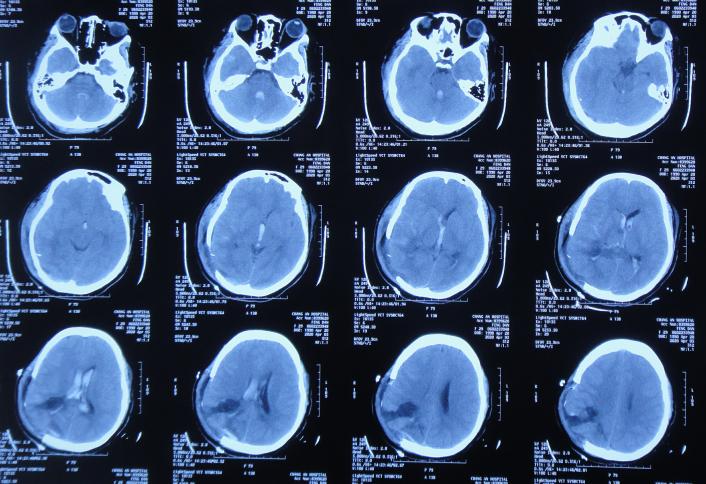

开颅术后次日即2020年4月3日,意识恢复,可简单言语,但左侧肢体偏瘫,仅可在床面平移,伴发热体温最高39.0℃;复查头颅CT示开颅术后去骨瓣状态,出血有减少,引流术后状态( 图-2 )。

图-2: 2020年4月3日头颅CT

开颅术后第3天即2020年4月5日,因出血明显减少,拔除了脑室外引流管( 图-3 )。

图-3: 2020年4月5日头颅CT